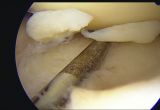

Die Arthroskopie ist ein minimalinvasives OP-Verfahren bei der über kleine Hautschnitte in "Schlüssellochtechnik" Erkrankungen und Verletzungen von kleinen und großen Gelenken versorgt werden. Dabei bedient man sich spezieller Optiken und kann über Monitore in gewünschter Vergrößerung Gelenkräume und (Gewebe-) Strukturen detailliert darstellen sowie mit Hilfe von Zusatzinstrumenten die erforderlichen Operationen schonend durchführen ohne das jeweilige Gelenk dafür größer offenlegen zu müssen. Durch die weiterentwickelten Instrumente und OP-Techniken lassen sich so auch aufwändigere Rekonstruktionen gewebeschonend durchführen. Die wesentlichen Gelenkbefunde werden mittels Bildgebung während der Operation dokumentiert.

Der Eingriff erfolgt in Vollnarkose. Über zwei winzig kleine Hautschnitte werden Portale für eine Optik und erforderliche Spezialinstrumente geschaffen und die hochaufgelösten, vergrößerten Bilder über eine Kamera auf einen Monitor übertragen. Je nach Befund erfolgt dann die Therapie. Liegt z.B. ein Meniskusriss vor, wird der „geschädigte“ Anteil, der die Schmerzen verursacht, soweit  entfernt bis nur noch gesundes, festes Gewebe vorhanden ist.Bei bestimmten frischen Rissformen ist eine Naht und damit der vollständige Erhalt des Meniskus möglich.

Hier kommen Techniken mit speziellen Nahttechniken und Nahtsytemen zum Einsatz. Knorpelverletzungen können ebenfalls durch verschiedene Techniken behandelt werden. Bei einem Kreuzbandriss kann eine Kreuzbandersatzoperation mit körpereigenem Sehnengewebe durchgeführt werden.  Auch korrigierende  Bandoperationen am Patellahalteapparat (bei wiederholtem Herausspringen der Kniescheibe) können so durchgeführt werden. Zum Abschluß der OP wird ggf. ein kleiner Drainageschlauch in das Gelenk eingelegt. Die Mobilisierung erfolgt zunächst an Gehstützen, zusätzlich wird eine Thromboseprophylaxe durchgeführt. Die Schonung und (Teil-) Entlastung des operierten Beines sind je nach Art des Eingriffes für eine unterschiedlich Lange Zeit erforderlich.